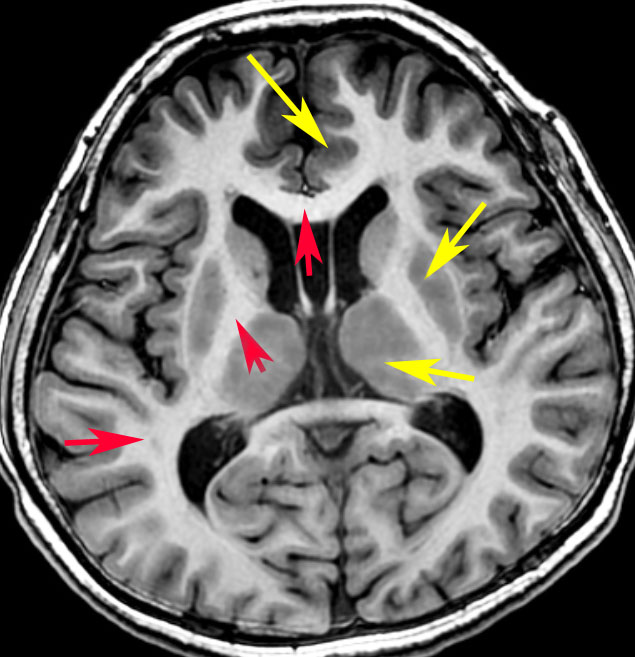

黄色い矢印が灰白質(灰色に見える),赤い矢印が白質です(白く見える)